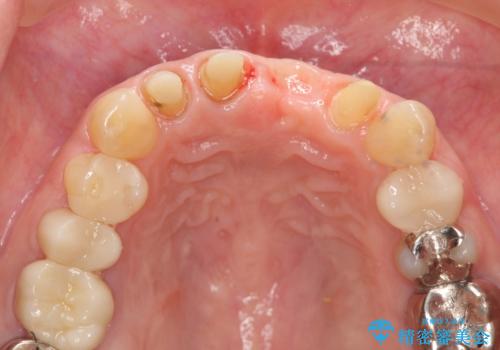

不良インプラントを除去し最終的にブリッジによる補綴で審美性の改善を行うこと、その準備として骨の造成・歯肉の移植による歯の欠損部顎堤のボリュームを維持・増大を計画します。

感染したインプラントからは排膿が間欠的に認められ、掻爬・除去が検討されうるような状況でした。

より審美的な改善を強く求められたため、インプラントを除去し可及的に欠損部顎堤を増大したのちブリッジによる審美改善を行いました。